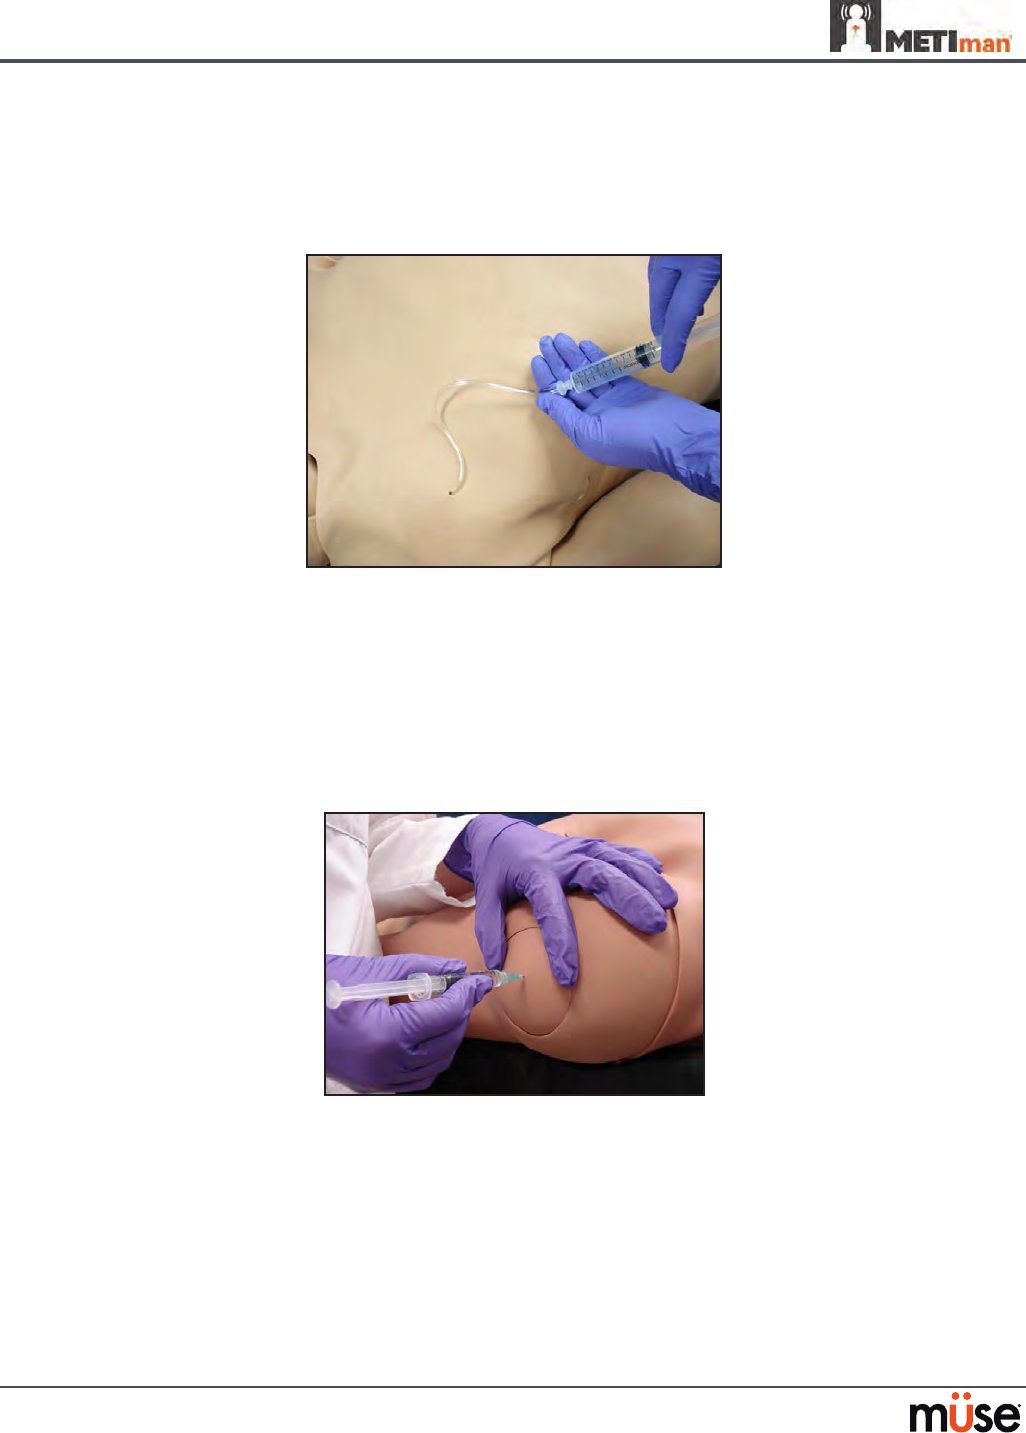

Intramuscular Injection

METIman allows for the administration of a deltoid intramuscular (IM) injection. Injection sites

are located on both of METiman’s arms. Use only a 20- to 22-gauge needle.

Intramuscular Injection